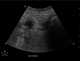

Dilated bladder

Urinary retention is an inability to completely empty the bladder. Onset can be sudden or gradual. [Source: Wikipedia ]